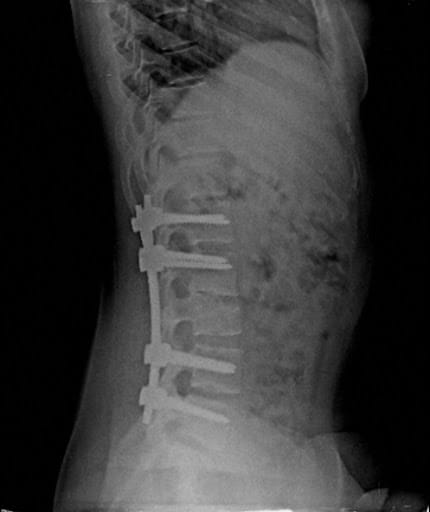

Surgical spinal stabilisation using rods and screws are reserved for “burst” fractures which are unstable, pose a risk of spinal cord injuries (or have already resulted in a spinal cord injury) or the the fractured vertebrae is too severely crushed to achieve any adequate restoration of the height of the vertebral body via minimally invasive procedures such as Vertebroplasty/ kyphoplasty.

In individuals upon whom spinal stabilization surgery is performed, the individual is allowed to get out of bed and start walking within 24 hours and can resume all activities within 2 weeks.